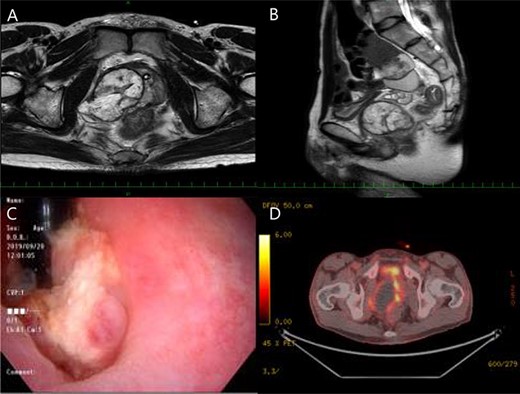

Macroscopically, a 55 × 55 × 50-mm soft solid tumor with necrosis and a bleeding smooth surface was visible in the prostate (Fig. 2A). There was no obvious adhesion between the tumor and bladder.

Macrospically, a 55 × 55 × 50-mm soft solid tumor with necrosis and a bleeding smooth surface was visible in the prostate (A), microscopically, the tumor was growing with invasive potential (B), and immunohistochemical results showed that CD34 were slightly positive (C), besides the Ki-67 labeling index was 20% (D).

Microscopically, the tumor was growing with invasive potential (Fig. 2B). It spread into the seminal vesicles and invaded the rectal muscularis propria. There was no tumor invasion of the bladder, and the surgical margin was cancer-negative. According to the examinations, gastrointestinal stromal tumor or solitary fibrous tumor was listed as differential disease. However, c-kit was negative and stat 6 was also negative, so both were denied. The Ki-67 labeling index was 20% (Fig. 2C). Immunohistochemical results showed that vimentin and CD34 were positive (Fig. 2D), whereas PSA was negative. The final diagnosis of PSS was reached based on histopathological results.